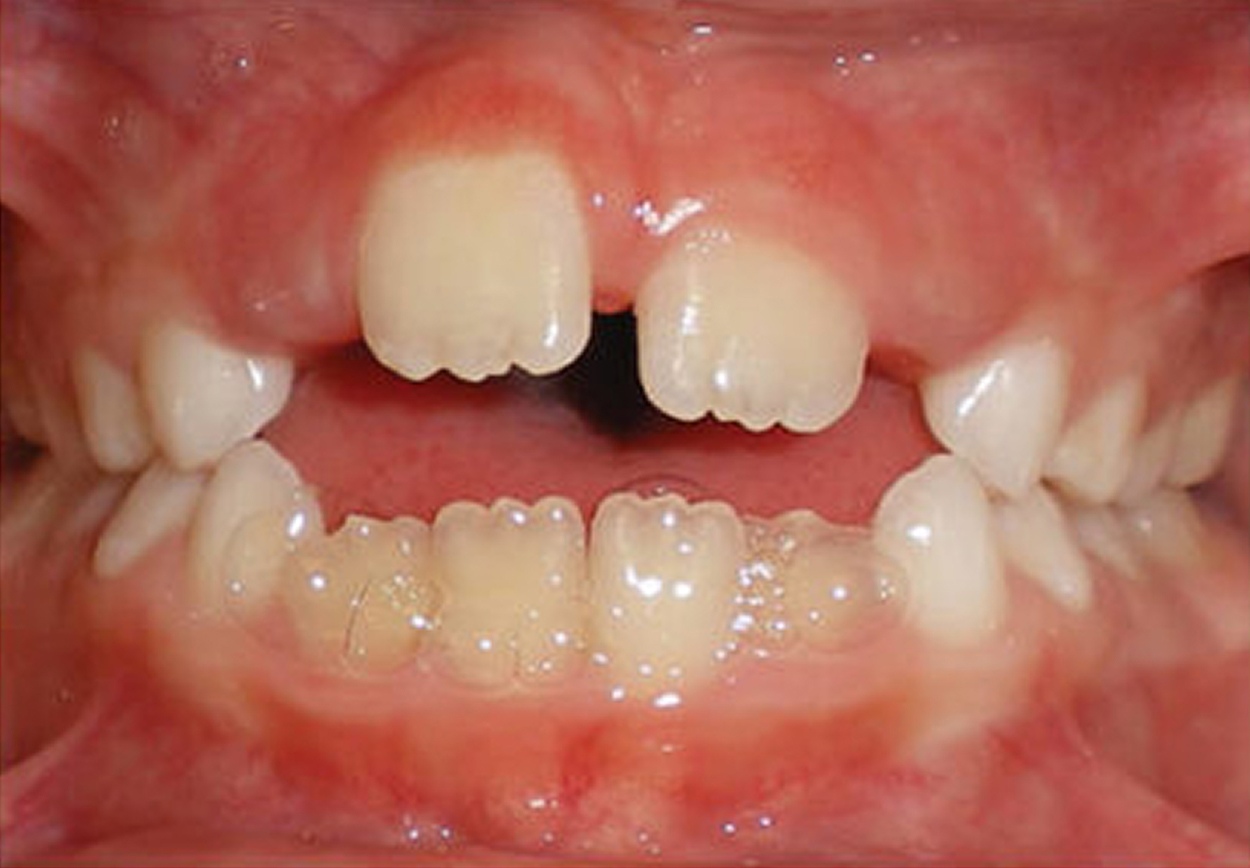

For many patients, an orthodontic intervention in Highland, NY or Ramsey, NJ can improve and sometimes eliminate these risks. Below are pictures of an OSA patient that benefitted from orthodontic treatment’s life-changing effects at Van Vliet & Ganz Orthodontics.